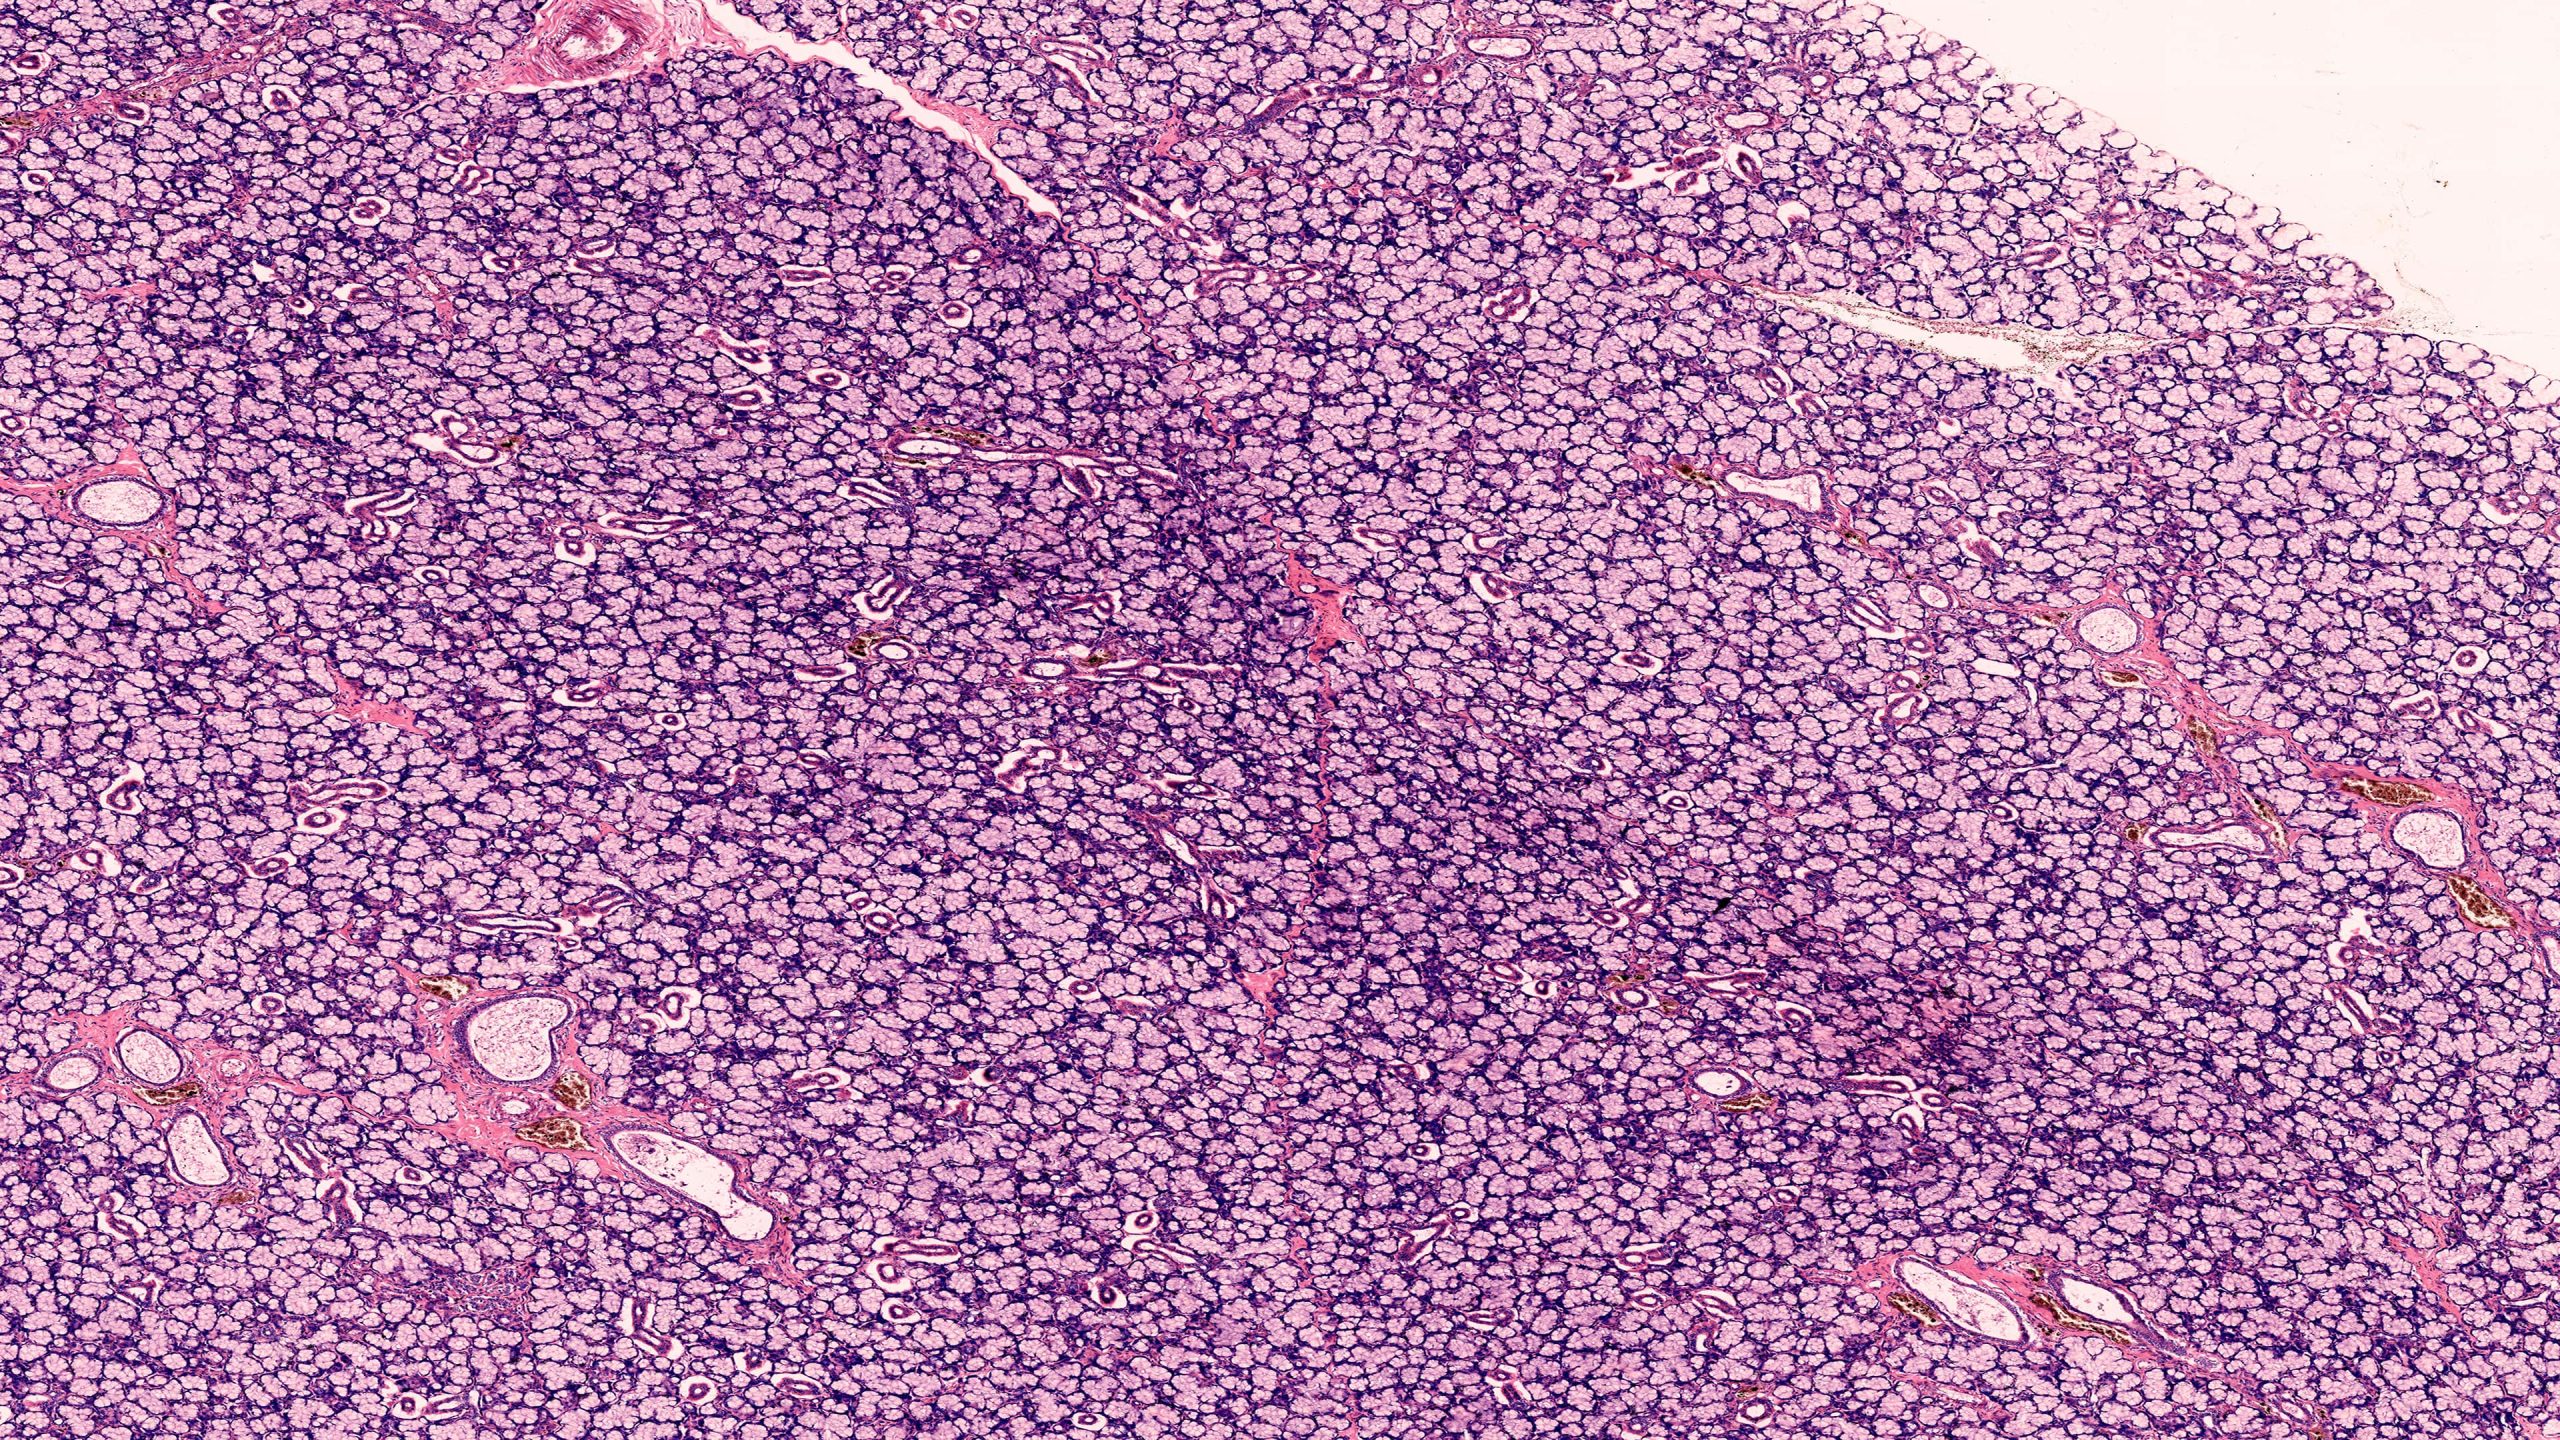

Mixed Salivary Gland 10X